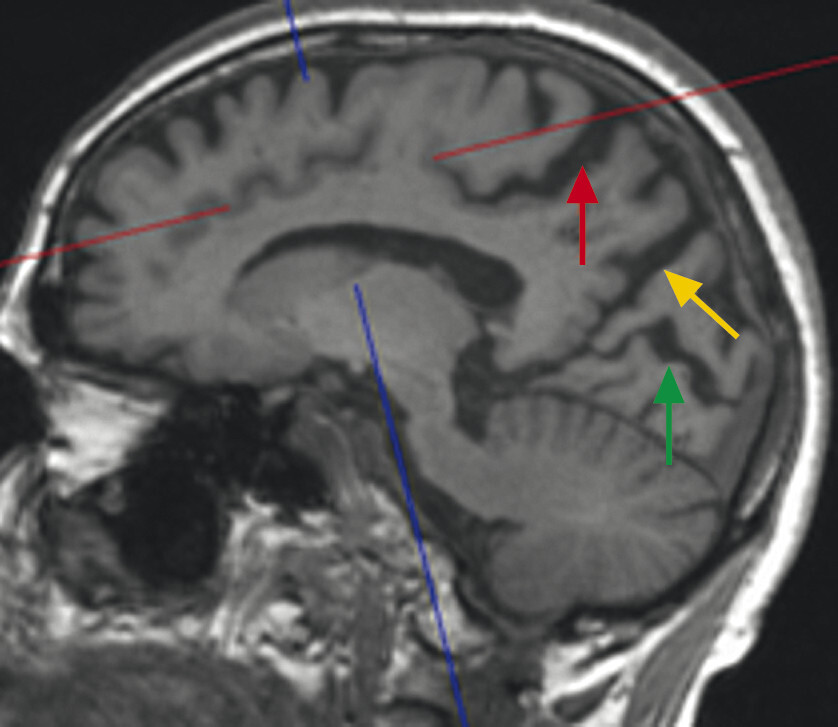

86-jähriger Patient mit schwerer posturaler Instabilität und Rapid-Eye-Movement-Schlafstörung. Bekannte Hyposmie, Obstipation, keine klassische hypokinetisch-rigide Klinik. Zusätzlich progressive Verschlechterung der kognitiven Fähigkeiten mit speziell visuokonstruktiven Problemen. Im MRT zeigen sich eine grenzwertige Hippokampusatrophie (a, Pfeile) und eine deutliche parietookzipitale Atrophie (b, c). Die deutliche Erweiterung der Pars marginalis des Sulcus cinguli (c, roter Pfeil), des Sulcus parietooccipitalis (c, gelber Pfeil) und des Sulcus calcarinus (c, grüner Pfeil) ist am besten auf T1w 3-D-Sequenzen in axialer und sagittaler Schichtung zu erkennen.

a Koronar reformatierte T1w MRT-Sequenz.

b Axial reformatierte T1w MRT-Sequenz.

c Sagittale T1w MRT-Sequenz.